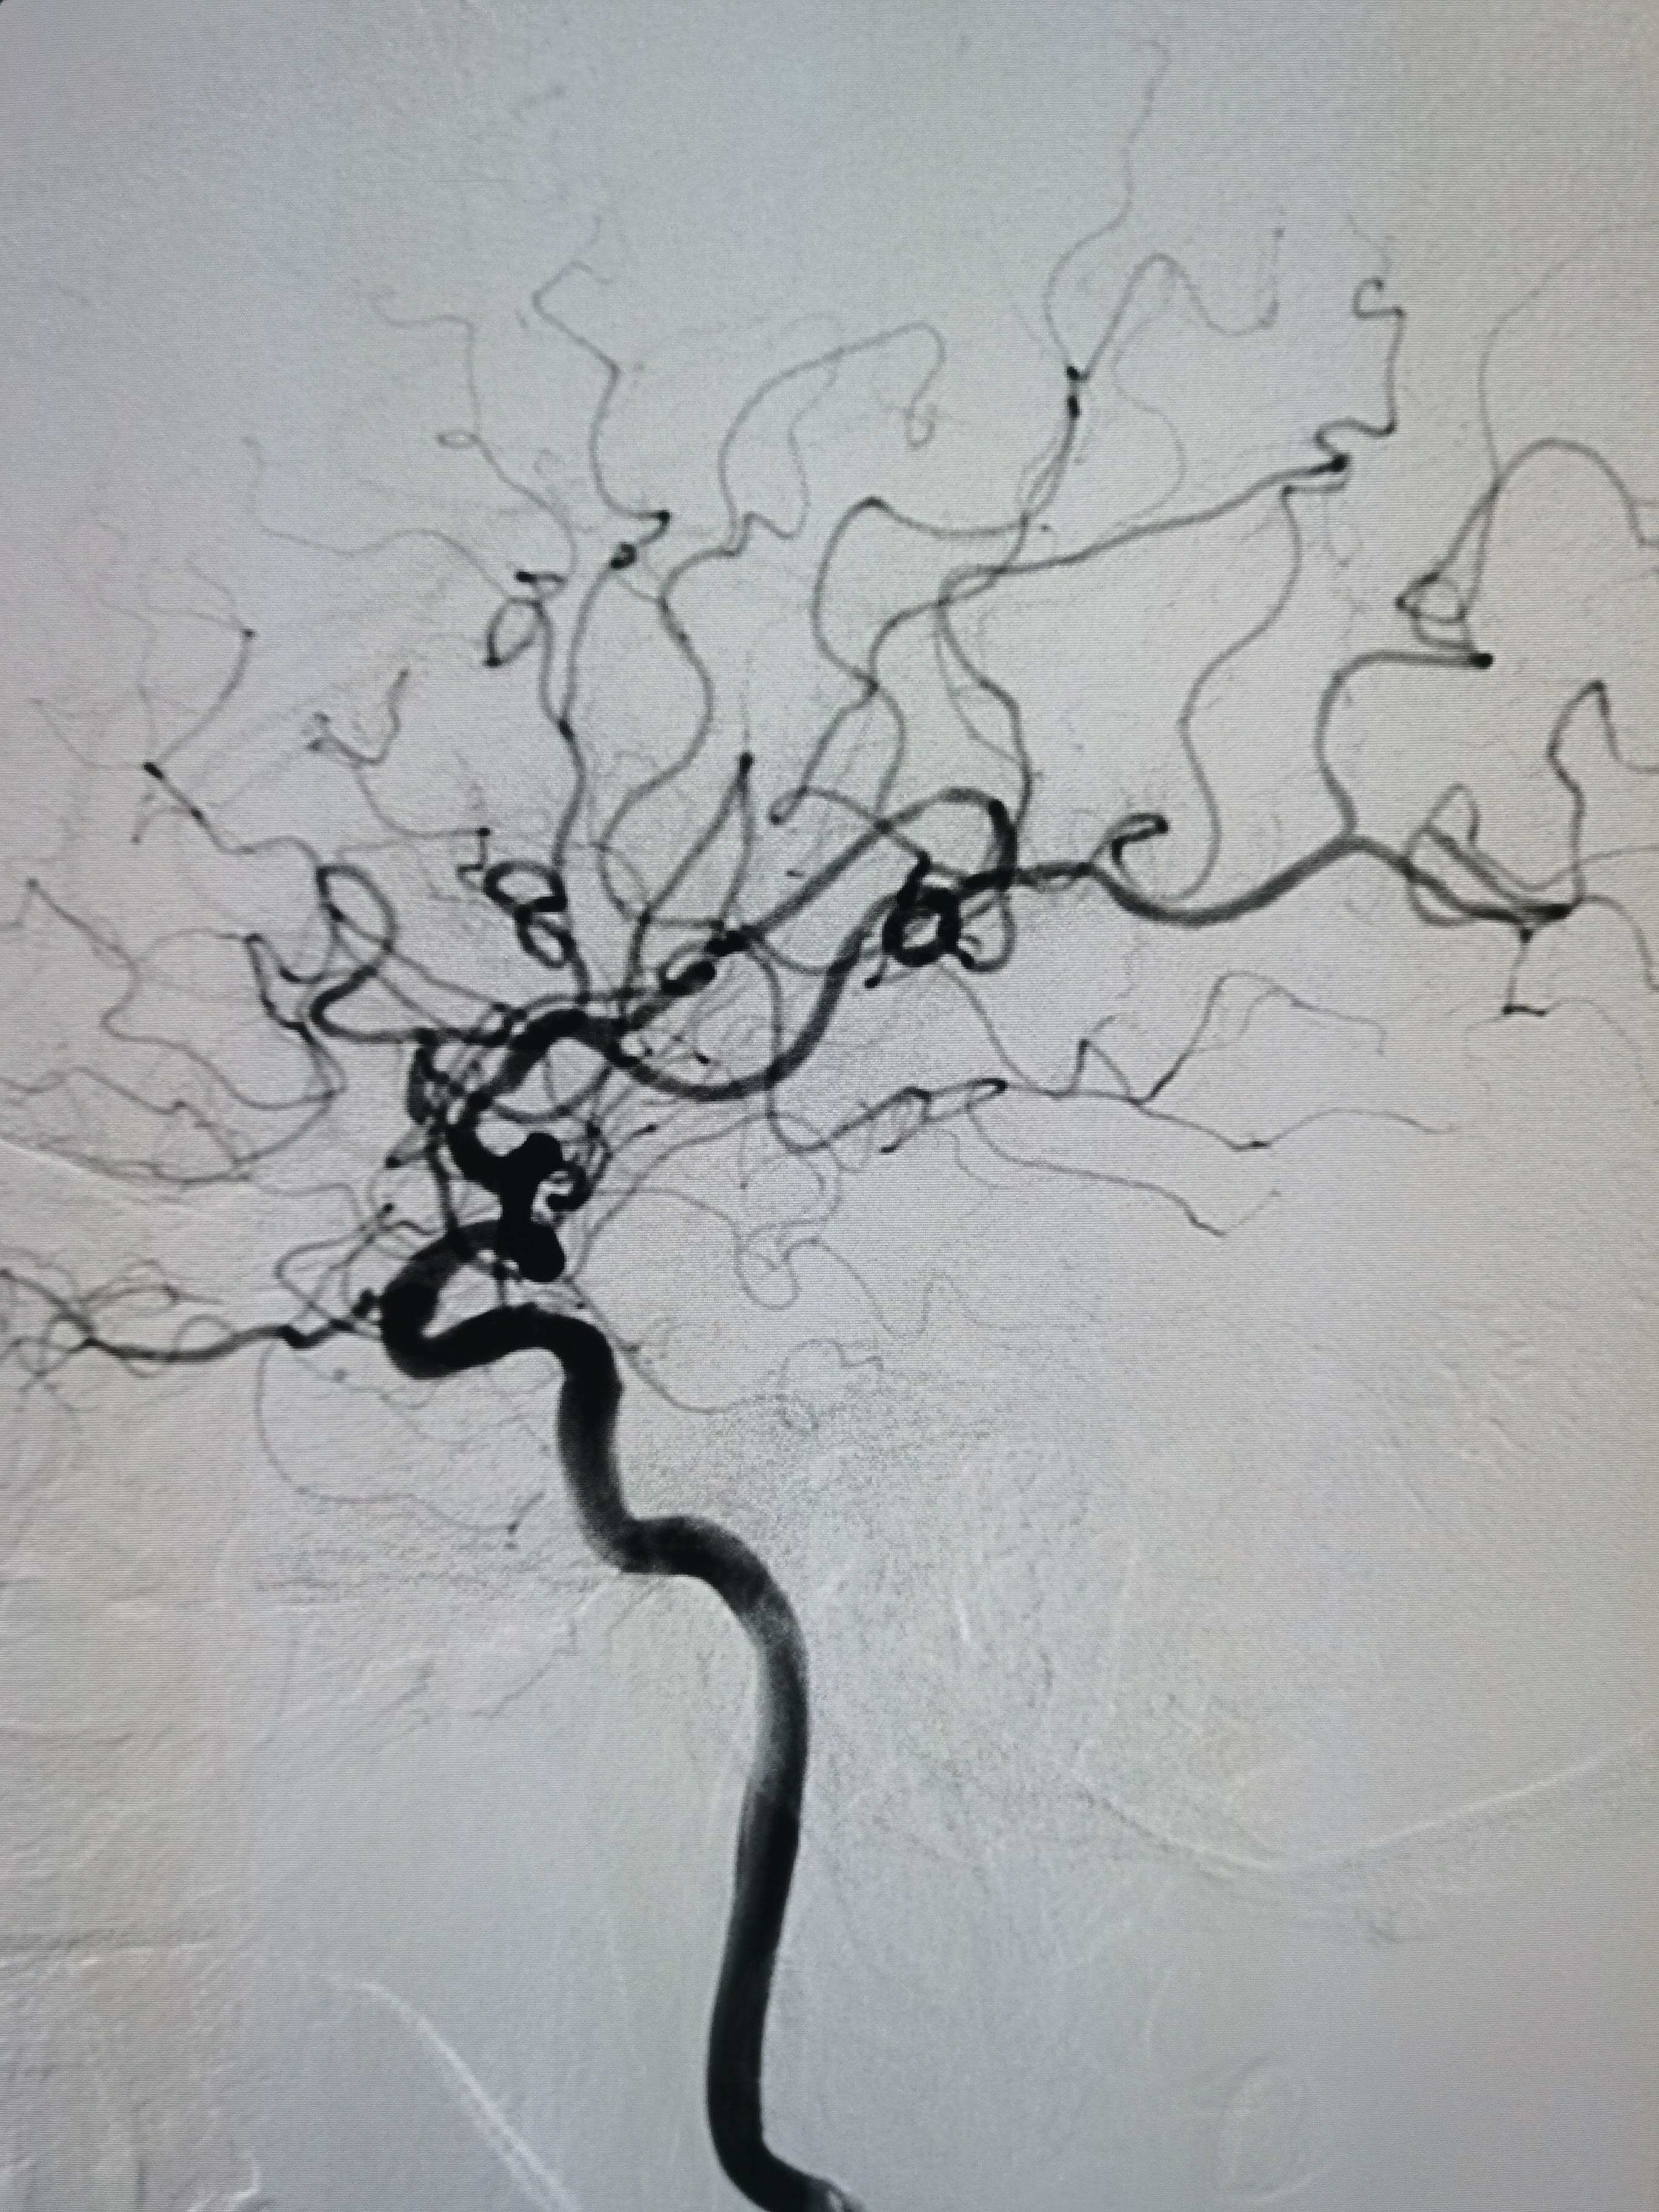

右侧大脑中动脉M1段重度狭窄。

右侧大脑中动脉M1段重度狭窄,病变处存在豆纹动脉。

患者右侧大脑中动脉M1段重度狭窄,病变处存在豆纹动脉分支,具备介入治疗指征,手术风险在于血管夹层,破裂及穿支闭塞可能,向患者家属详细交代病情及风险后,家属积极要求介入治疗。拟行右侧大脑中动脉球囊扩张备支架成形术。